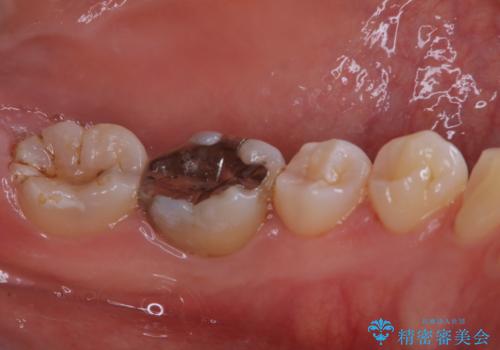

- これからインビザラインでのマウスピース矯正が始まるので、歯石取りをしてほしいとのことでした。

PMTC60分コースを行いました。

プラーク(細菌の塊)や歯石がたまると歯の表面はザラつきいてきます。そのザラつきは歯周病や虫歯菌の棲家となります。そのまま放置すると、歯肉が腫れてきたり、歯肉から出血したり、口臭が強くでたりします。とくに歯肉の境目は、歯磨きで汚れを除去することが難しく、プラーク(細菌の塊)や歯石が溜まりやすい場所です。

歯並が、がたついている場合はなおさら汚れが溜まりやすいです。矯正治療前や矯正中、定期的にPMTCをすることで、矯正治療中の歯肉トラブルを防ぐことにつながります。